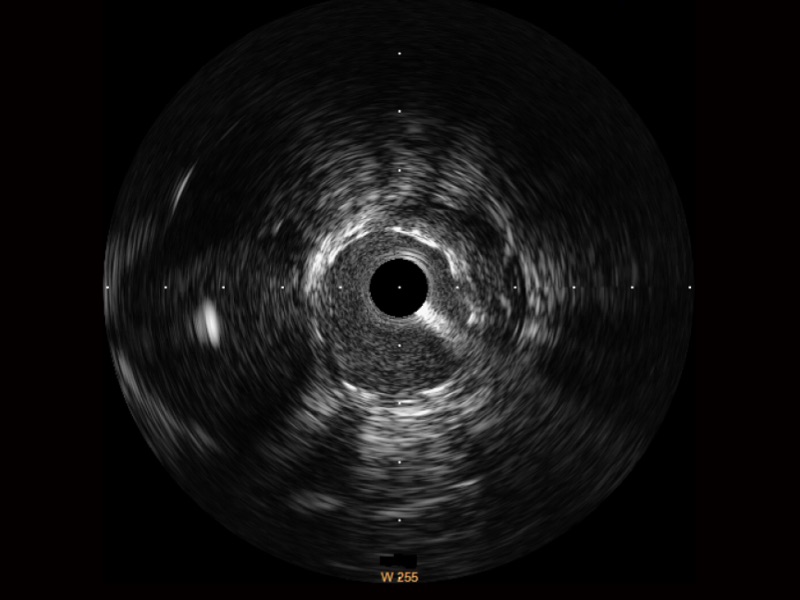

玖鼎集团超宽频成像技术覆盖20-80MHz1或20-90MHz2频率范围, 提供优异的分辨力同时也保证充足的穿透深度

对比传统IVUS导管成像,玖鼎集团宽频IVUS图像的近场支架梁显影更细腻,远场中膜外血管仍清晰可辨,兼顾远中近,兼顾分辨力与穿透深度